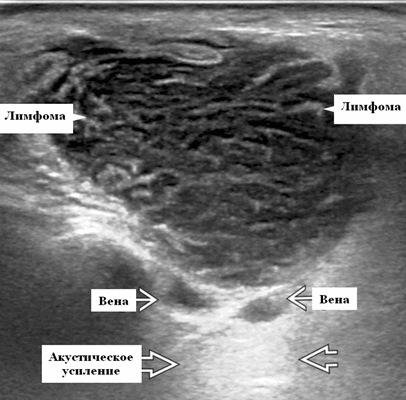

Серошкальное УЗИ. Узловая НХЛ. Одиночные или множественные увеличенные яйцевидные внутрипаротидные лимфатические узлы. Гомогенно гипоэхогенный по отношению к паренхиме околоушной железы. Сетчатый эхосигнал. Заднее акустическое усиление. Первичная паренхиматозная НХЛ. Рассеянный, неоднородный эхосигнал; нечеткие, гипоэхогенные, похожие на опухоль участки. В пунктате внутрикистозная или паренхиматозная кальцификация из-за конечной стадии воспалительного изменения. Небольшие кистозные области образуются из-за сдавления терминальных протоков лимфоидной гипертрофией. Множественные небольшие гипоэхогенные участки (представляют собой лимфоидные агрегаты), разбросанные на фоне ткани слюнной железы. Изменения могут имитировать хронический сиалоаденит и диагноз часто ставится при биопсии. На УЗИ необходимо искать аналогичное поражение других слюнных и слезных желез, фон синдром Шегрена, BLEL. Может иметь или не иметь перипаротидную и шейную лимфаденопатию

- Используя современные датчики высокого разрешения, несмотря на их солидную природу, лимфоузлы НХЛ имеют тенденцию к заднему усилению

- При ультразвуковом сканировании лимфоузлы неходжкинской лимфомы показывают интранодальный ретикулярный / микронодулярный рисунок с использованием более новых датчиков с высоким разрешением

Обычно на УЗИ это гипоэхогенный лимфоузел по сравнению с соседними мышцами и ранее описывалось как псевдокистозные узлы с задним усилением. При использовании более старых преобразователей внутренние эхосигналы в узлах были очень низкими, почти анэхогенными, напоминающими кисту. Используя современные датчики высокого разрешения, несмотря на их солидную природу, мы видим, что узлы НХЛ имеют тенденцию к заднему усилению. Равномерная клеточная инфильтрация внутри узлов создает меньше границ между структурами и облегчает прохождение ультразвука. Это, в сочетании с низкой внутренней эхогенностью, приводит к так называемому псевдокистозу. Лимфоузлы неходжкинской лимфомы показывают интранодальный ретикулярный или микронодулярный рисунок с использованием более новых преобразователей высокого разрешения